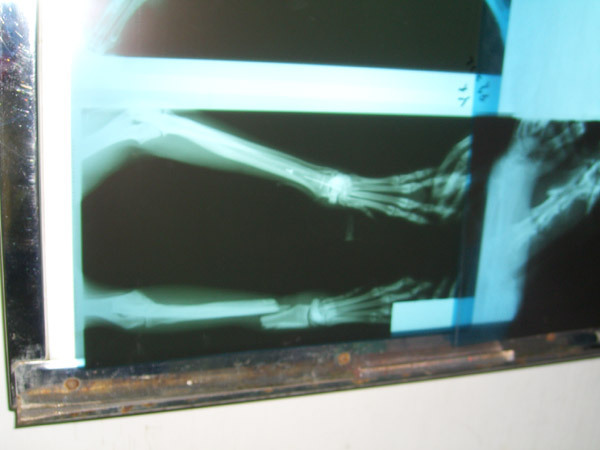

左前腳橫向斷掉

X光等,費用25000元 (你沒看錯,就是二萬五,已經是某些人的一個月的薪水了)

但現在狗狗很虛弱,要等到晚上或明天才會照X光及開刀

阿嗚左前腳已經開完刀了,醫生花了5個小時開刀

阿嗚現在左前腳用板模固定,右前腳打點滴

因為照X光發現阿嗚右下顎也骨折,因為骨折造成嘴巴裏產生一個洞